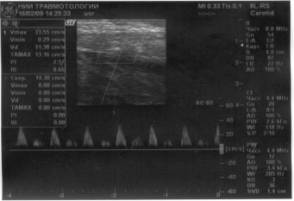

Рис.2 Эхограмма того же пациента, после

операции трансплантации красного костного мозга в область регенерата

большеберцовой кости. Отмечается повышение активности остеогенеза (А).

Допплерогамма сосуда в регенерате, отмечается усиление кровотока.(Б)